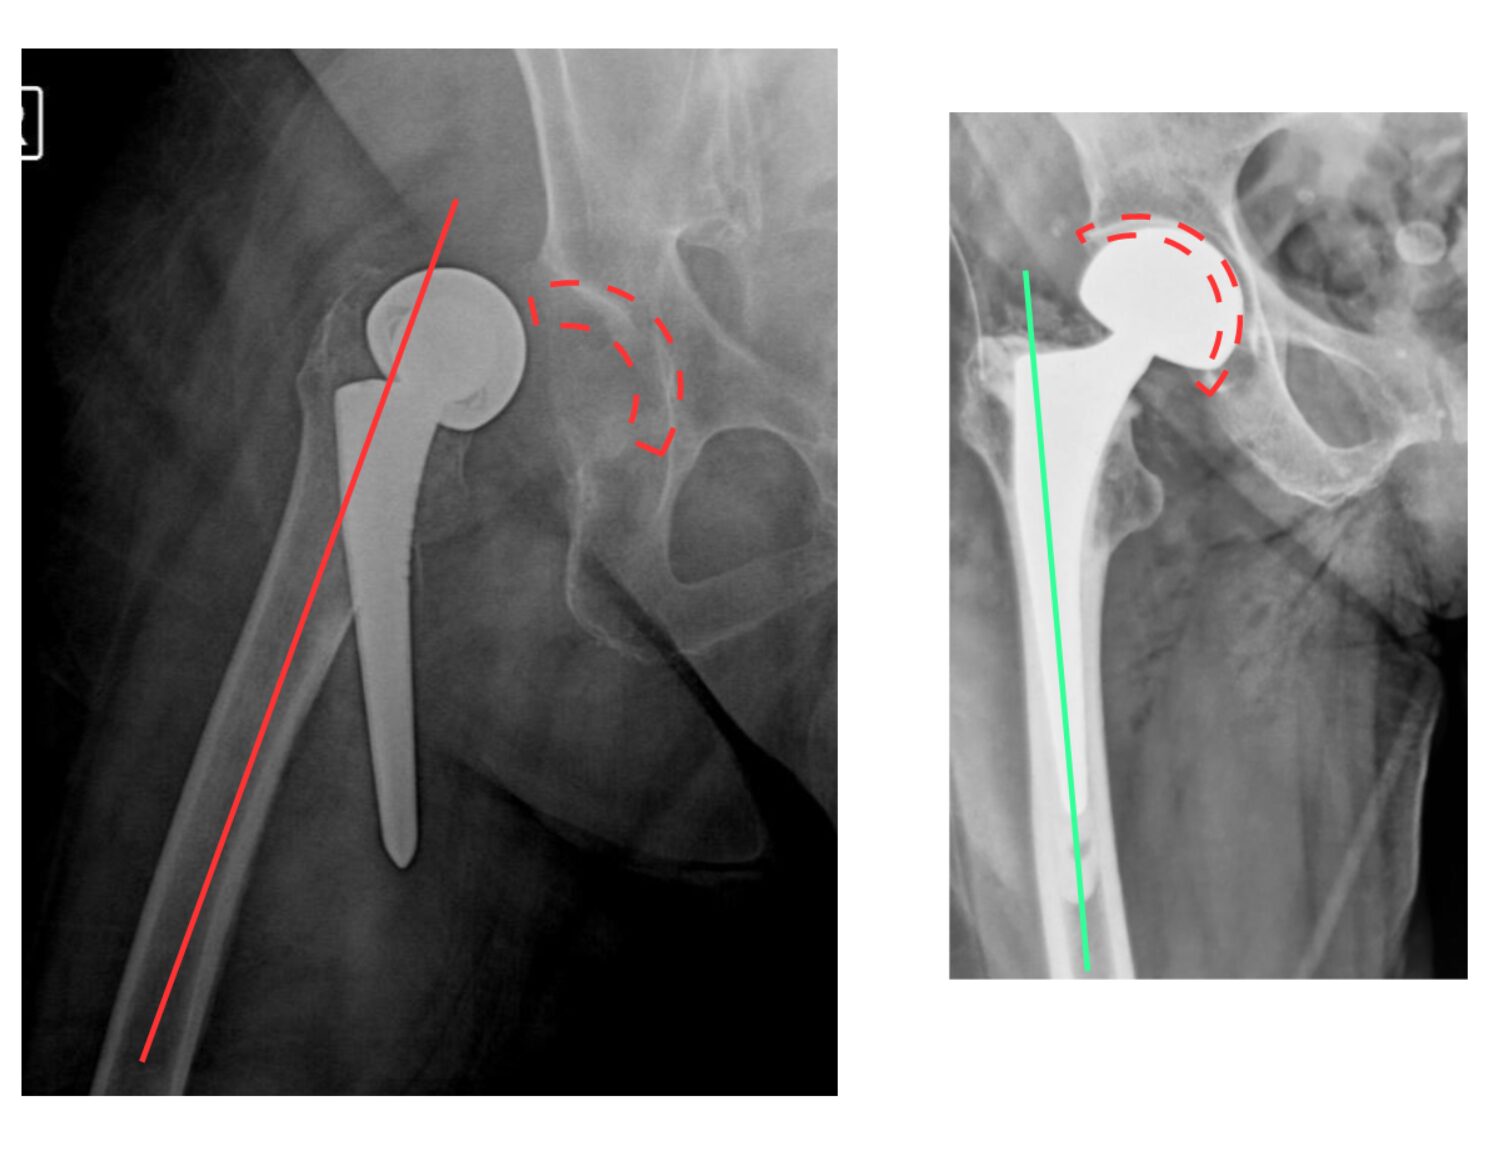

Χωρίς ικανή εμπειρία, επιπλοκές μπορεί να συμβούν: στην εικόνα 13, στην αριστερή πλευρά ημιαρθροπλαστική AMIS στην οποία τοποθετήθηκε ολόκληρος ο στυλεός του μηριαίου εκτός του αυλού. Ο ασθενής κινητοποιήθηκε την επομένη με αφόρητο πόνο σε εξάρθρημα. Όσο κι αν φαίνεται απίθανο, είναι μια επιπλοκή που μπορεί να συμβεί σε μη έμπειρα χέρια. Δεξιά στην εικόνα φαίνεται ο ορθός τρόπος τοποθέτησης του στυλεού.

Στην εικόνα 14, κατά τη διάρκεια ημιαρθροπλαστικής AMIS, η απειρία οδήγησε σε εργώδεις προσπάθειες ανάταξης και κάταγμα κοτύλης. Αντιμετωπίστηκε στην κλινική μας με ειδικού τύπου πρόθεση κοτύλης του τύπου της αναθεώρησης αρθροπλαστικής (revision hip arthroplasty)